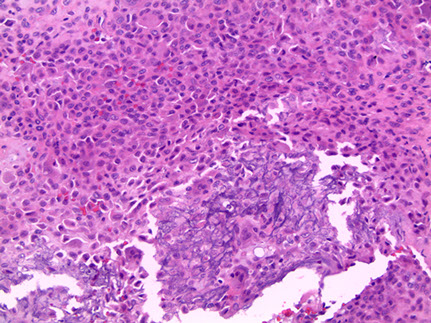

Hyperparathyroidism - Brown tumors. Right image shows zone of bone resorption in center c defect filled c fibroblastic tisuue, and around the periphery is osteoid-producing area that looks like fibrous dysplasia. Image on left is close of area replacing fibroblastic tissue c lots of osteoclast-like GCs, that may lead to misdiagnosis of giant cell tumor (except GC tumors usually lack fibrogenic stroma)

Brown Tumor

Bone loss causes microfractures and hemorrhage causing macrophage influx and reparative fibrous tissue

Brown from vascularity, hemorrhage and hemosiderin deposition

"Brown tumors" of bone are caused by hemorrhage and hyperparathyroidism

- may also be caused by pseudohyperparathyroidism, but is usually due to parathyroid adenoma, hyperplasia, or rarely carcinoma or chronic renal failure

Micro: Osteoclasts line cystic spaces (tunneling), which also have a very fibrous stroma, inc formation of woven bone, and peritrabecular fibrosis, MNGCs